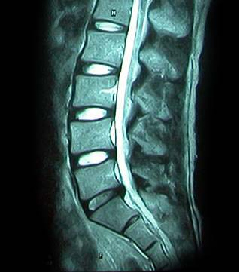

64세 여자환자는 2개월 전부터 요통과 다리 바깥쪽과 발등, 종아리 뒤쪽으로 저린 감각이 심해져서 개인병원에 들러 평가 및 물리치료를 받았으나 별다른 호전이 없고, 1주일 전부터는 허리를 숙이거나 물건을 들 때, 오래 걸을 때 통증이 더 심해져서 본원을 방문하였다. 12년전 집안일을 심하게 하고 난 후부터 간헐적인 요통을 발생하였으며, 별다른 치료 없이 지냈으며, 4년전 무거운 물건 들고 난 후 심하게 요통과 둔부의 통증까지 발생하여 MRI 촬영상 L1-2, L3-4-5, L5-S1 HNP와 Lt. L4 & both L5 nerve compression, Lt. S1 nerve compression 진단받고 Epidural steroid injection을 받고 통증 경감되었고, 간헐적으로 통증이 발생하였으나 별다른 치료 없이 헬스클럽에서 지속적인 운동으로 관리하였다.

• 척추 방사선 사진1